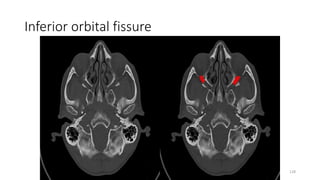

Inferior orbital fissure

Content

• Inferior ophthalmic veins

infraorbital artery

infraorbital vein,

• Tributary of pterygoid plexus

• Zygomatic nerve and infraorbital

nerve of maxillary nerve (V2)

• Orbital branches

of pterygopalatine ganglion

128

146